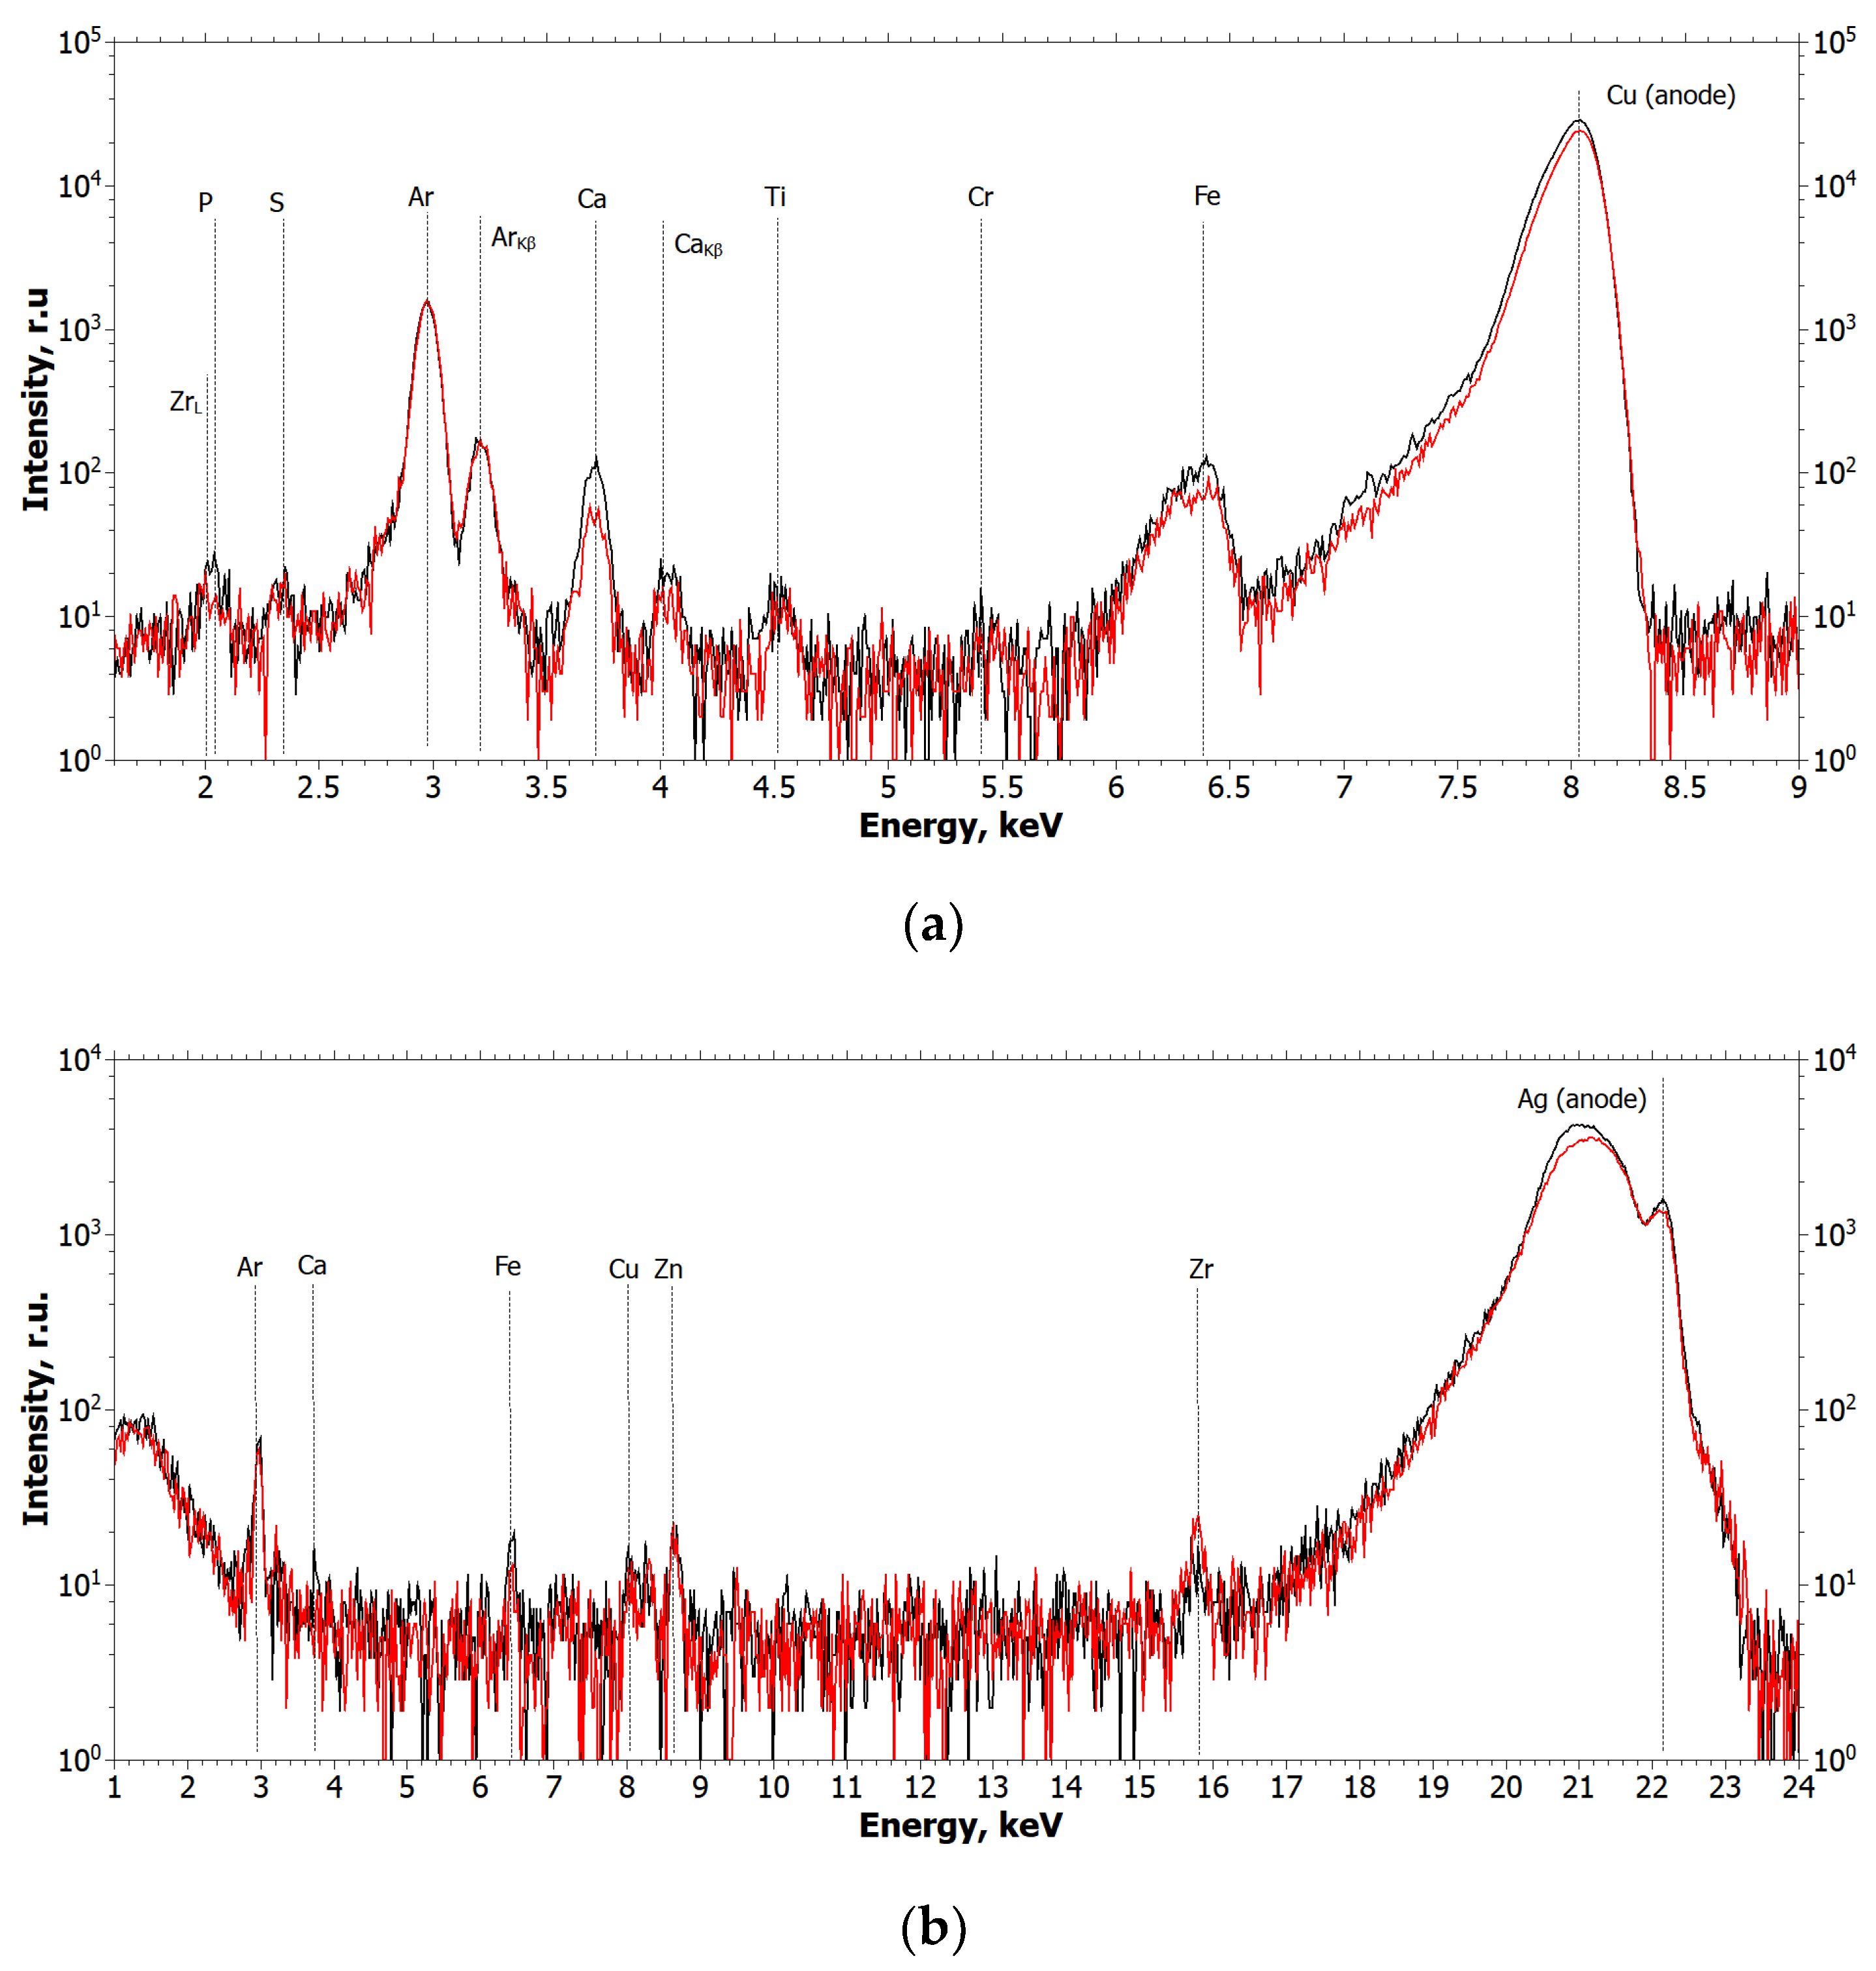

2.1.1. Results of X-ray and Electron Microscopic Studies

4.3. X-ray Fluorescence Analysis (XRF)

- Cu tube (focus size 12×2.0 mm), 40 kV × 40 mA mode;

- Monochromator—silicon (symmetrical), reflection (111);

- Wavelength—1.54 Å (E = 8.047 keV);

- Beam size—10.0×1.0 mm (slits adjustable);

- Detector—Amptek 123SDD (Amptek, Bedford, MA, USA);

- Exposure—1200 s per measurement.

- Ag tube (focus size 10 × 1.0 mm), 40 kV × 40 mA mode;

- Monochromator—silicon (symmetrical), reflection (111);

- Wavelength—0.55 Å (E = 22.162 keV);

- Beam size—10.0 × 1.0 mm (slits adjustable);

- Detector—Amptek 123SDD (Amptek, Bedford, MA, USA);

- Exposure—1200 s per measurement.